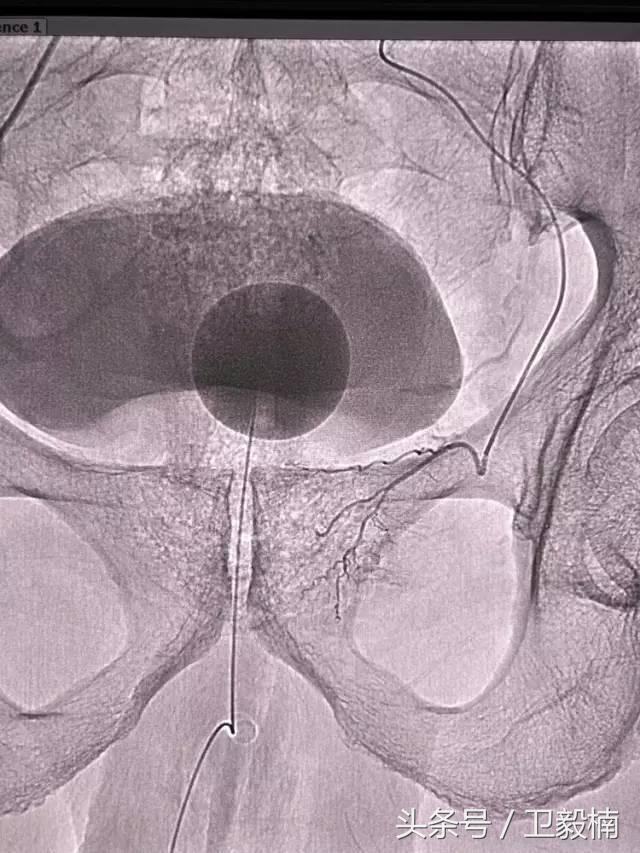

(1)选择性肿瘤供血动脉灌注化疗+栓塞治疗恶性肿瘤。

(3)应用栓塞术治疗海绵状血管瘤,蔓状血管瘤,子宫肌瘤,骨肉瘤,鼻咽部纤维血管瘤等。

七、子宫肌瘤、子宫腺肌症、宫外孕、输卵管阻塞引起的不孕症等妇产科疾病;